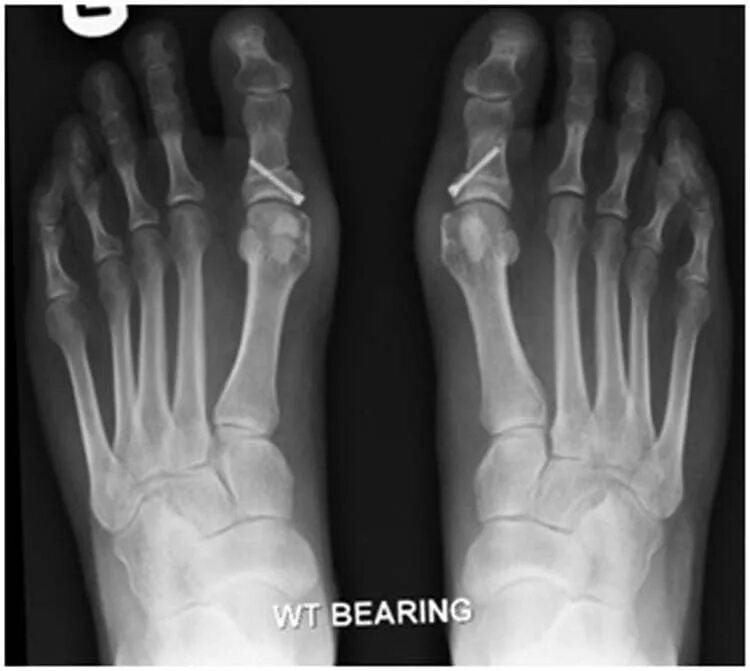

Операция деформации пальцев стопы